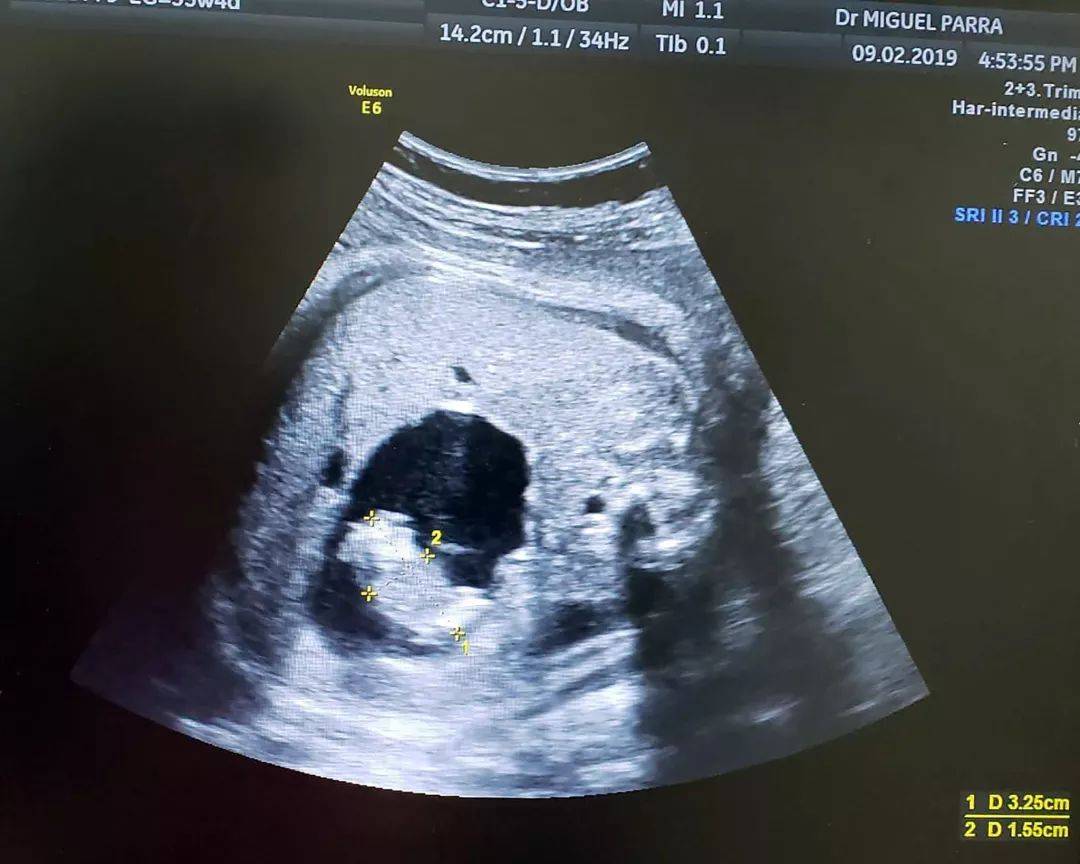

伊扎玛拉宝宝刚出生时,腹中还有一个胎儿(Dr. Miguel Parra-Saavedra)

在彩超和3D/4D超声影像图上,帕拉·萨维德拉医生发现,图中充满液体的区域中,实际上含有一个非常小的胎儿;同时,还有一条独立脐带将小的胎儿连接在大的双胞胎的肠子上,并为小胎儿供血。

超声扫面的结果显示出位于子宫内的胎儿腹中,有一个正在成形的双胞胎小胎儿(Dr. Miguel Parra-Saavedra)